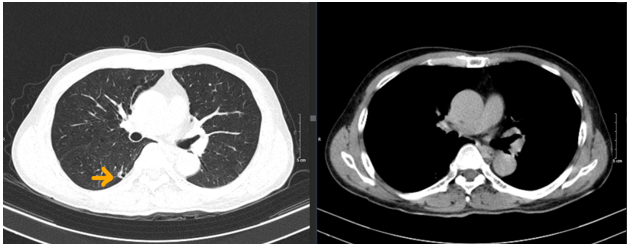

- Chụp cắt lớp vi tính lồng ngực:

Hình 2. Hình ảnh chụp CLVT lồng ngực: nhu mô thùy trên phổi phải có nốt đặc đường kính khoảng 6mm (mũi tên vàng).